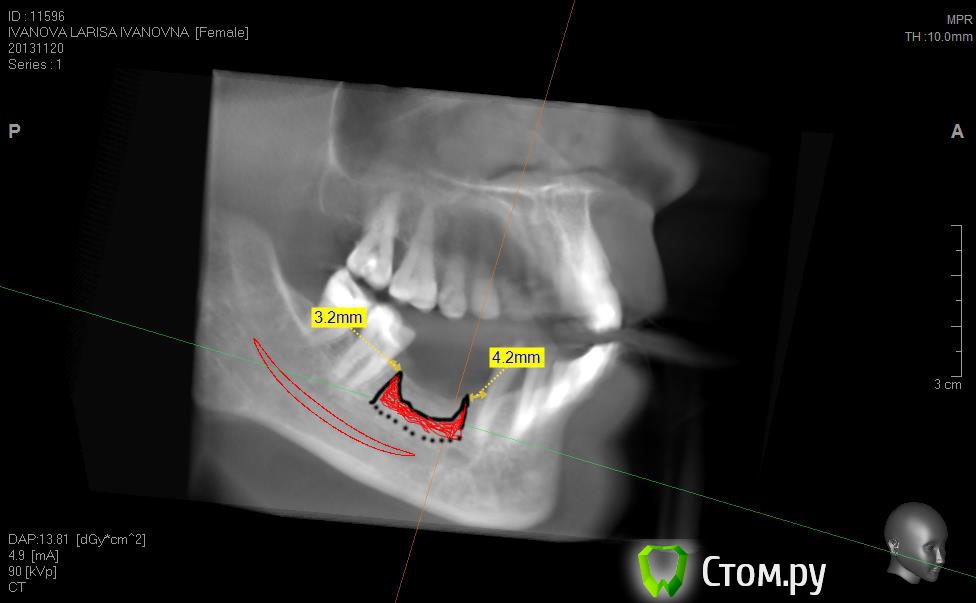

Neilrus Опубликовано 2 марта, 2014 Поделиться Опубликовано 2 марта, 2014 (изменено) Здравствуйте, коллеги, уделите 6 минут новичку…у меня тут проблема, она абсолютно не проблема для того, кто хоть пару раз делал расщепление гребня,а я вот только курсы закончил и у меня планируется через 7 дней операция. Вроде все понял, но пока стремаюсь.Посморите снимки, пожалуйста, а я напишу тот протокол, который хочу применить, как на курсах понял, поправьте, если что не так )) Спросил бы у лектора, но ведь так всегда, да?)Планирую иплантаты по месту 45,46 зубов.Гребень узкий в обл 45 з и близко нч нерв, как раз поднимается к ментальному отвертстию. С этим и связан страх. Никаких транспозиций делать пока не готов. В арсенале нет пьезотома пока, вот пару таких операций сделаю и куплю.Планирую поставить 4,2*8 для 45 зуба и 4,2*11,5 для 46 зуба (Мis Seven) . Соединю коронки, т.к. премоляр коротковат. Итак, план по захвату таков:1)Разрез чуть язычнее середины гребня, откидываем слиз-надк лоскут с аккуратностью в области менталиса.2)По центру гребня делаем горизонтальный распил сепарационным диском диаметром 7 не доходя до зубов по 3 мм. Глубина распила получается 3,3. Потом беру диск 10 и глубина уже 4,8.3)Мелким 7мм диском делаю дистально вертикальный распил на глубину 3,3 длиной с длину имплантата моляра 11,5, а медиально тем же диском на длину 4-5 мм, ниже страшно, боюсь нерв задеть. На верхушке гребня соединяем распилы (черные линии на моем рисунке). Делаем бором твердосплавным шаром компактостеотомию в преполагаемом месте перелома.4)Берем долото и вставляем в горизонтальный разрез и постукиваниями молоточка продвигаем его на глубину до 8мм по всей длине разреза (длина миниального импланта). Чуть покачивая из стороны в сторону, при этом убирая закругления от диска внутри горизонтального распила. (На рисунке, который сам нарисовал – это красная зона).5)Немного раздвинув края в месте предполагаемых имплантатов пилотом 2мм прохожу на глубину имплантатов. Проверяем параллельность.6)Загоняю по очереди мисовские компрессионные винты на глубину имплантатов до диаметра третьего винта 2,4- 3,7 (т.к. импланты 4,2)7)Теперь они вроде как должны быть нормально раздвинуты ( здесь я не понял, нужно проходить фрезами из хир набора или так хорошо войдут) Может финишной фрезой пройти хотя бы на всю глубину имплантатов? Подскажите, пожалуйста.8)Дальше заполняю пустоты MP3, фиксирую пинами MCT 2.75 мембрану evolution толстую на 2 мм ниже коспактостеотомии, перекидываю на язычную сторону под надкостницу краешек запихиваю.9)Мобилизую лоскут, ушиваю все наглухо и надеюсь на лучшее. ВОПРОСЫ:1)не коротковат ли имплант 4,2*8, но ведь я соединю их? Можно немного наклонить его медиально, выход шахты оставить там же, но апикальную часть ближе к моляру, тогда длина 10 выйдет, но там и так не получается соостно с зубами имплант размстить, а тут его и такая ангуляция, не хорошо, я думаю.2)Отслойка лоскута медиально- правильно я написал или порвется тогда и лучше рассечь связку на 44 и медиально вниз.3)Фрезы хирургические нужно использовать при нормальном раздвигании краев гребня? Кстати, нормально-это сколько для диаметра имплантата 4,24)Язычно нужно как-то дополнительно фиксировать мембрану?5)MP3 мешать с аутокостью и кровью из ловушки?6)Как лоскут мобилизовать медиально рядом с ментальным нервом? Пластика зкпд будет одновременно с открытием.Спасибо вам за ваше время ) Изменено 8 мая, 2014 пользователем Bier Ссылка на комментарий